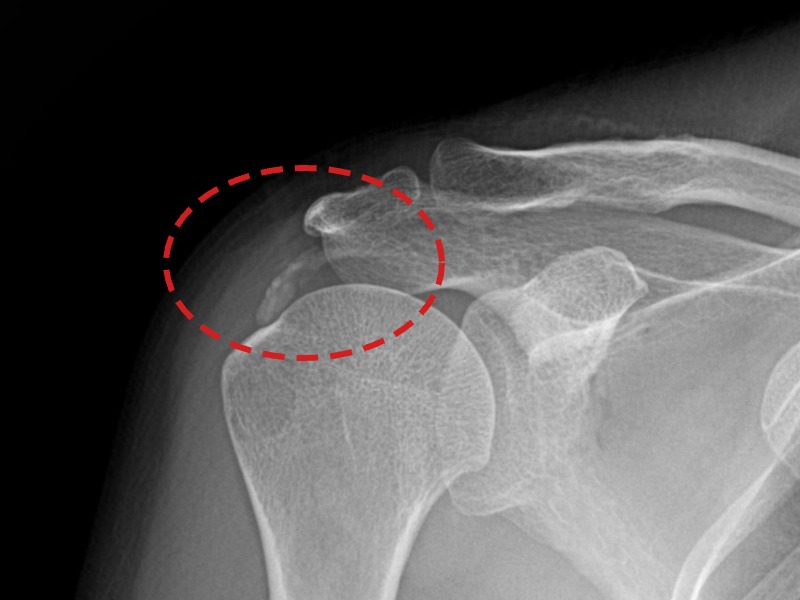

[촬영시기:21.09.02~21.10.07]

[석회분쇄흡입술] 좌측 어깨 통증으로 팔을 옆으로 올리기 어려워진 60대 남성 환자로, X-ray에서 좌측 극상근건 내 석회 침착이 확인되어 석회분쇄흡입술을 시행하였습니다.